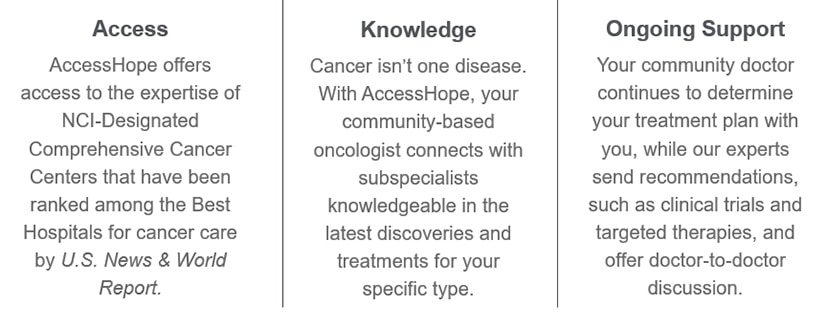

AccessHope provides associates enrolled in a Blue Cross of Idaho medical plan with confidential, cancer support services at no cost when you access the benefit. If you or an eligible family member (spouse/domestic partner, children (under and over age 26), parents, parents-in-law, grandparents, grandparents-in-law and siblings) is diagnosed with cancer, AccessHope connects you and your local treating oncologist to specialized experts at world-renowned National Cancer Institute (NCI)-designated comprehensive cancer centers including:

You also have access to compassionate oncology nurses who offer information, empowerment and support when people need it most.

Why You Should Contact Access Hope